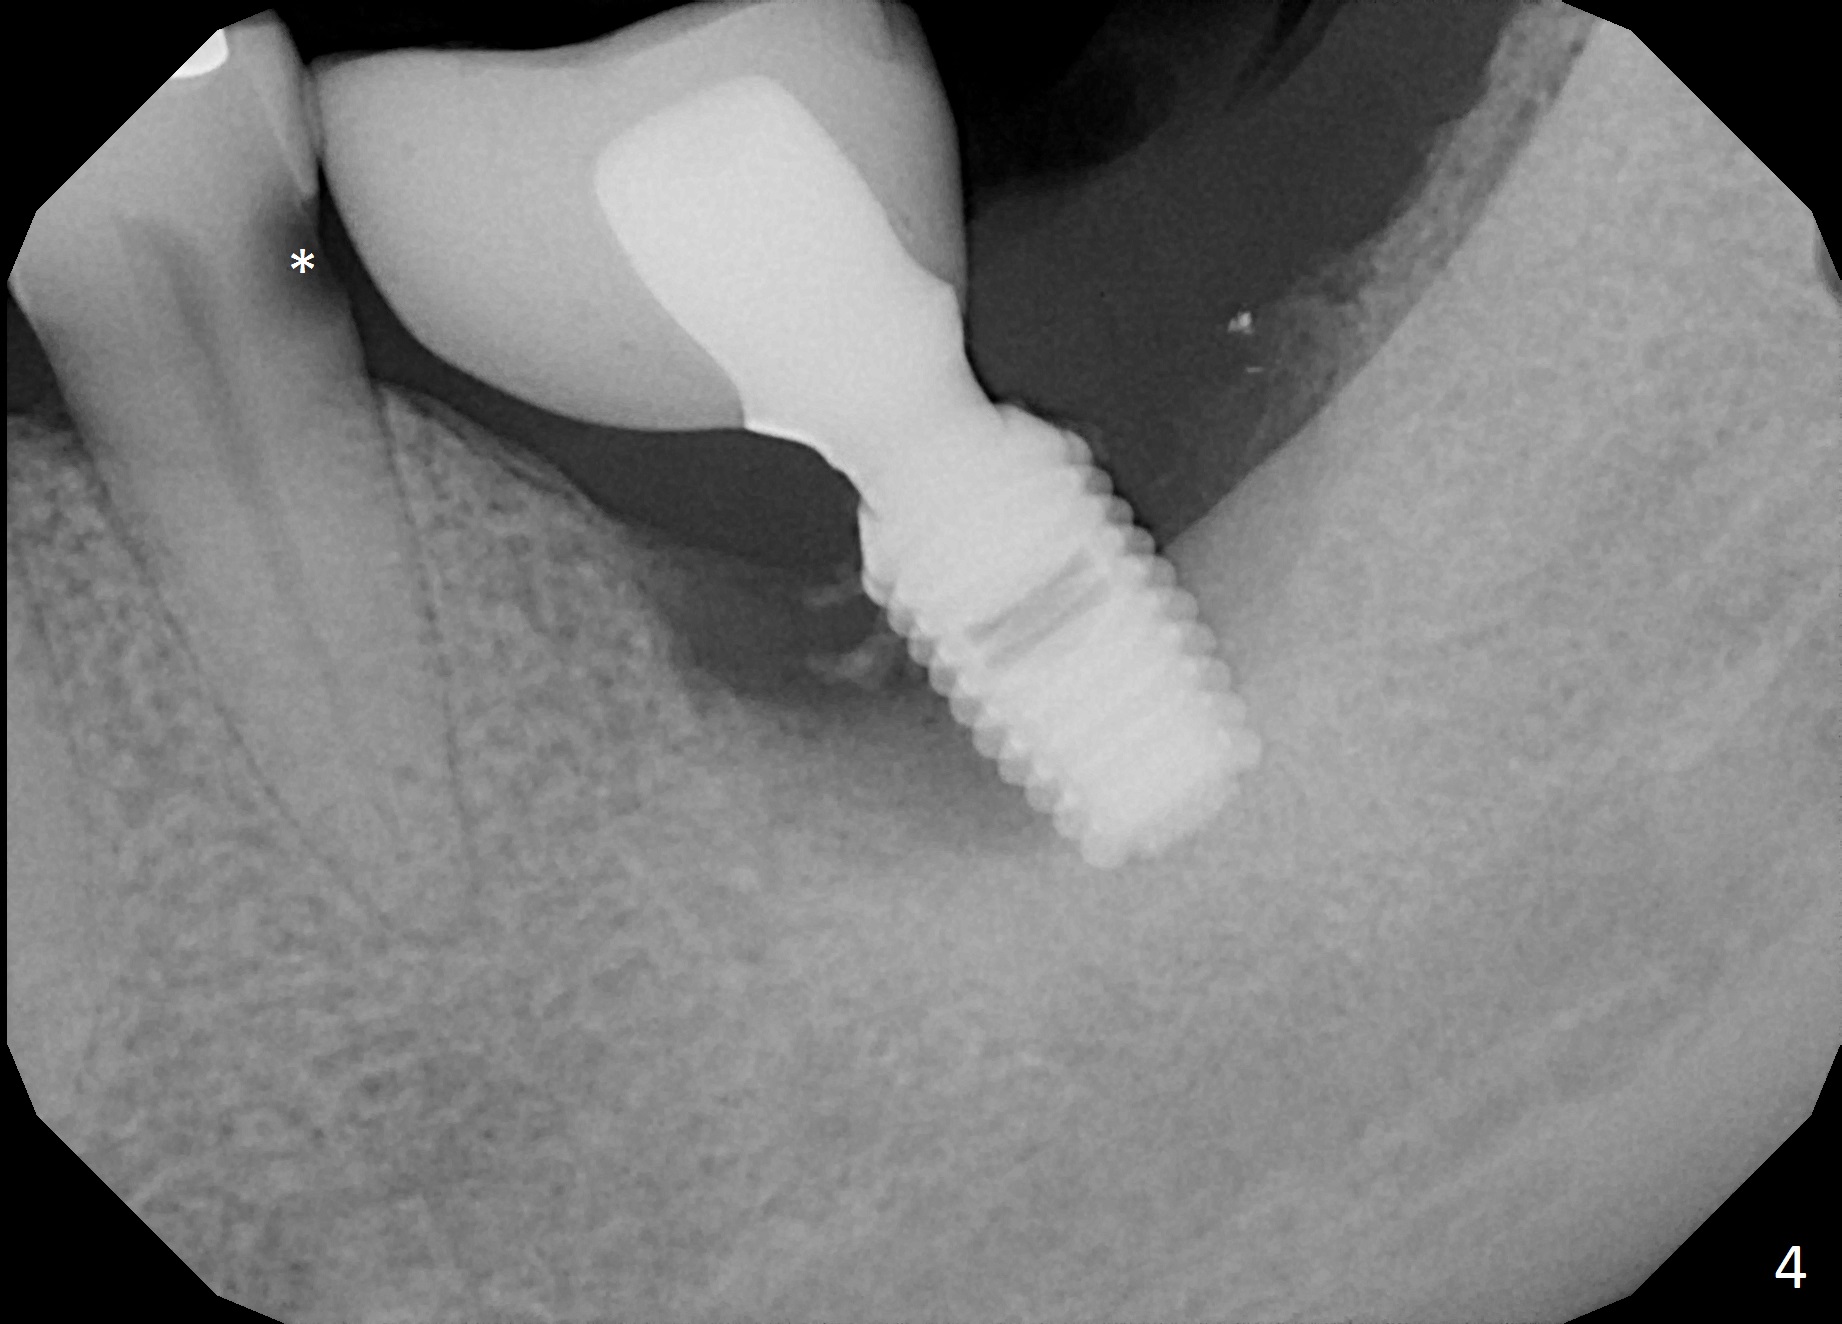

Etiology of Periimplantitis A 42-year-old woman presented to clinic 11 years ago with history of extraction of the tooth #19 two months earlier (Fig.1). Two months later, a 5x8 mm Bicon implant was placed (Fig.2). Integrated Abutment Crown was delivered 2 years later (Fig.3) with persistent radiolucency in the mesial socket. The tooth #18 was extracted with socket preservation 7 years ago. Recently she returned with chief complaint of chewing pain in the lower left for a while. The buccal gingiva of #19 is erythematous, edematous and tender (Fig.4). There are healing abutment at #29 and implant crown at #30. Periimplantitis at #19 is most likely due to buccodistal placement. When it is removed (Clindamycin), a smaller IBS or SM implant will be placed immediately and mesiolingually (Fig.3). For better wound protection with periodontal dressing or provisional, an implant will be placed at #18 at the same appointment. Draw blood for PRF if the vein is large enough. Surgical stents have been in cold sterilant. Return to Lower Molar Immediate Implant, Prevent Molar Periimplantitis (Protocols, Table), Course 1 2 Fig.1 Remedy Xin Wei, DDS, PhD, MS 1st edition 06/16/2017, last revision 06/26/2020 |